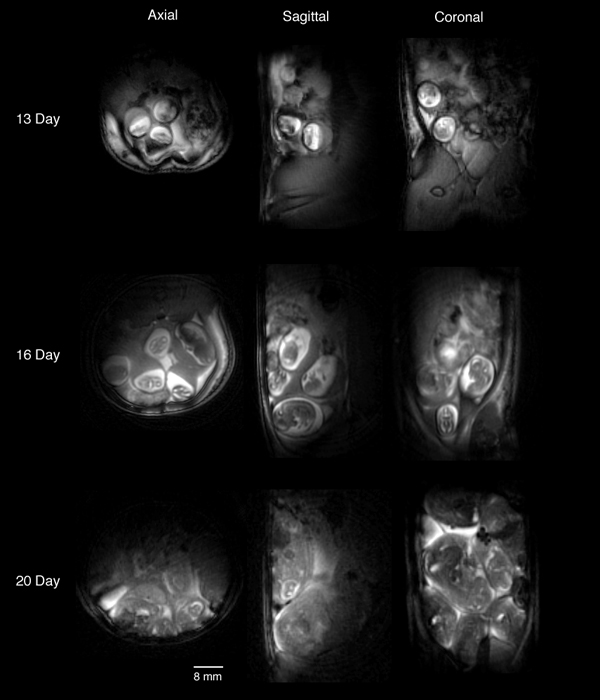

The first published images of time-course imaging of embryos in-utero using magnetic resonance imaging. The images show the uterus of a single pregnant rat at three different times during gestation of the embryos. (Smith, Shattuck, Hedlund and Johnson. Magn Res Med, 39:673-677, 1998).